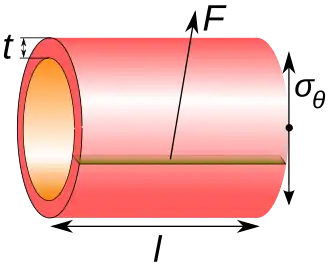

Regardless of site, blood pressure is related to the wall tension of the vessel according to the Young–Laplace equation (assuming that the thickness of the vessel wall is very small as compared to the diameter of the lumen):

where

- P is the blood pressure

- t is the wall thickness

- r is the inside radius of the cylinder.

- is the cylinder stress or "hoop stress".

For the thin-walled assumption to be valid the vessel must have a wall thickness of no more than about one-tenth (often cited as one twentieth) of its radius.

The cylinder stress, in turn, is the average force exerted circumferentially (perpendicular both to the axis and to the radius of the object) in the cylinder wall, and can be described as:

where:

- F is the force exerted circumferentially on an area of the cylinder wall that has the following two lengths as sides:

- t is the radial thickness of the cylinder

- l is the axial length of the cylinder